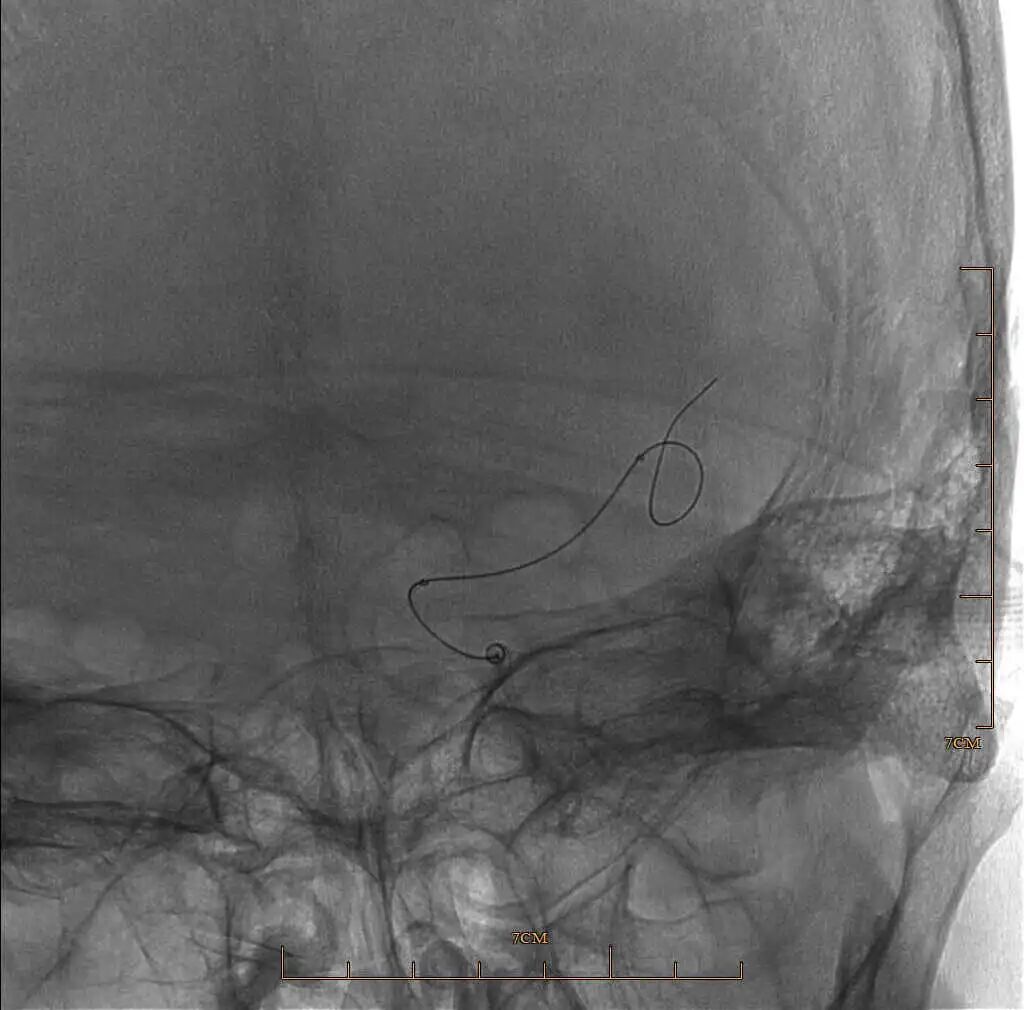

90cm Locaste 088输送导管建立路径,造影提示左侧大脑中动脉M1段闭塞。

动脉长鞘怎么置入有励可说|Locaste 088励楷长鞘及Tarvos微导丝在左侧大脑中动脉闭塞取栓术中的应用_https://www.jmylbn.com_新闻资讯_第8张

动脉长鞘怎么置入有励可说|Locaste 088励楷长鞘及Tarvos微导丝在左侧大脑中动脉闭塞取栓术中的应用_https://www.jmylbn.com_新闻资讯_第9张

动脉长鞘怎么置入有励可说|Locaste 088励楷长鞘及Tarvos微导丝在左侧大脑中动脉闭塞取栓术中的应用_https://www.jmylbn.com_新闻资讯_第10张

Tarvos微导丝携微导管超选大脑中下干M2末端。